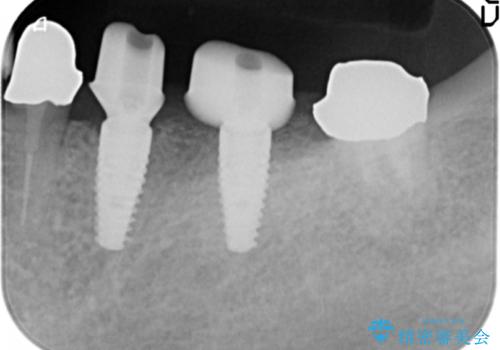

X線写真より、過度な咬合支持負担により支台となる歯の周囲の骨吸収が認められます。今後安定してしっかりとかめるような環境を整備するためにインプラント治療を選択しました。

- 100万円(ストローマンインプラント×2・仮歯×4・チタンカスタムアバットメント×2・ジルコニアクラウン×4)費用は治療当時の料金となります

ブリッジ治療は支台となる歯が弱いと、今回のように周囲の骨が吸収したり歯が割れてしまったりといったトラブルがおきます。咬合力に対抗するため、今回はインプラントを用いて機能回復を行いました。